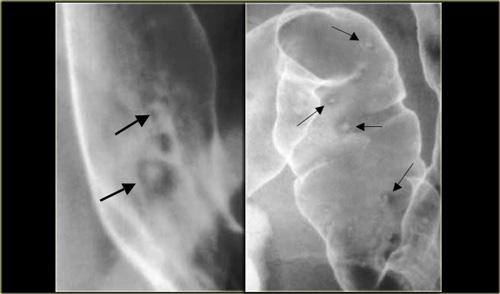

Viêm thực quản do Crohn

Hình bên trái là một bệnh nhân mắc bệnh Crohn.

Có hình ảnh viêm thực quản dạng u hạt với các ổ loét áp-tơ (mũi tên).

Đây là biểu hiện không thường gặp của bệnh Crohn.

Hình bên phải cho thấy các ổ loét áp-tơ đại tràng, là biểu hiện phổ biến hơn.

Viêm thực quản do Cytomegalovirus

Hình bên trái là một bệnh nhân AIDS bị viêm thực quản nhiễm trùng do Cytomegalovirus.

Các ổ loét khổng lồ như vậy cũng có thể do HIV đơn thuần gây ra.